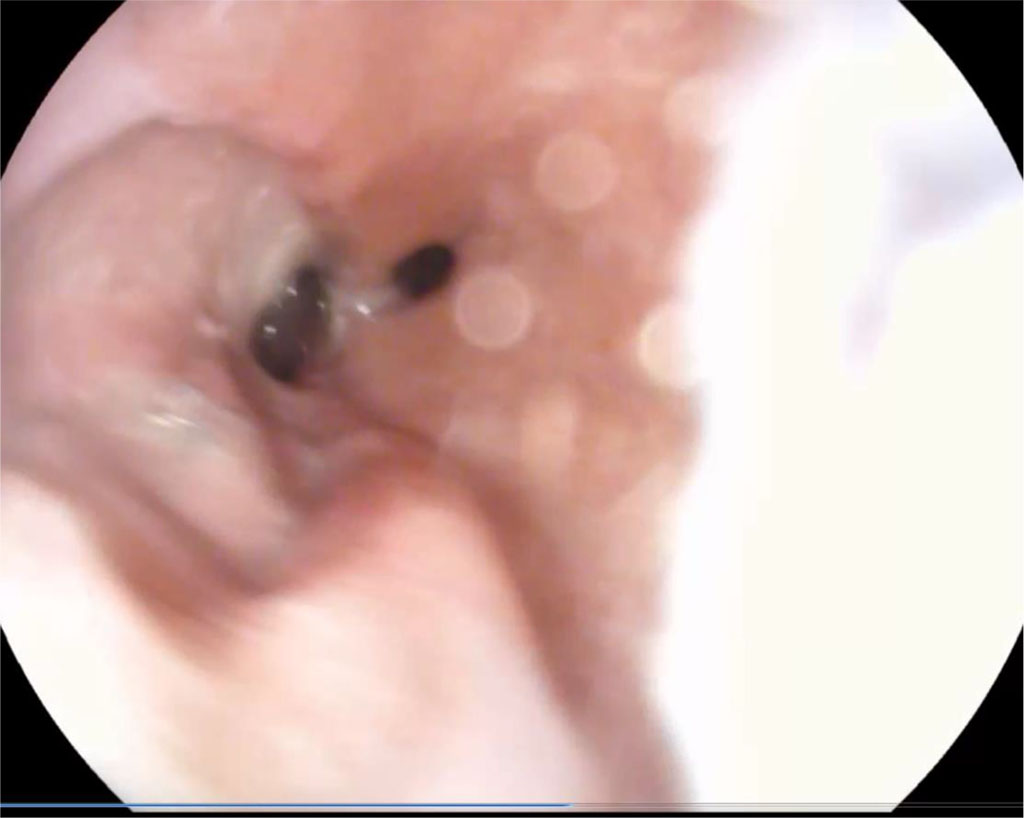

Day 21, after endoscopic sanitation of the abscess cavity (once every 2 days) on an outpatient basis. Further, a significant decrease in size of the abscess cavity and fistula orifice was noted. Fig. 2.

Figure 2. 21 days after surgery (explanations in the text)